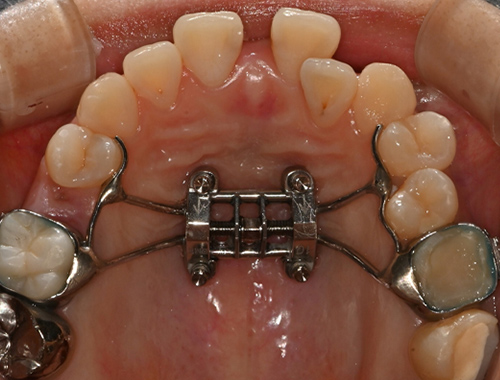

비수술 악궁확장 치료 MARPE (Miniscrew-assisted rapid palatal expansion)

덧니의 근본적인 원인은 치아 크기에 비해서 뼈의 크기가 작기 때문입니다.

청소년기가 지나간 성인에서는 뼈의 크기를 늘리기 어렵지만 이지민 대표원장은 가능합니다.

확장 후

확장 후

이지민 원장은 성인 비발치 교정의 핵심인 비수술 악궁 확장 가능성을, 직접 연구한 논문 결과를 바탕으로 사전에 정밀 분석·예측합니다.